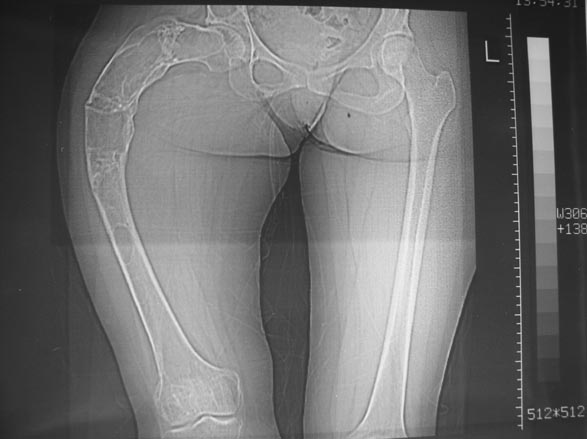

Женщина 28 лет, Больна с 12 летнего возраста, Когда после адекватной травмы получила перелом бедра. На рентгенограммах выявлено какое-то (рентгенограмм и документов нет) изменение бедренной кости, была оперирована, имеется гистологическое заключение - фиброзная дисплазия.дСформировалась деформация бедра. На сегодня - Укорочение 7см. Грубая деформация бедра по типу "пастушьей палки", последний патологический перелом в январе 2004г., консолидировавшийся при консервативном лечении. Имеются грубые изменения и в надвертлужном массиве.-- С уважением, Leonid

Возможна аппаратная коррекция оси с формированием клиновидного регенерата, которая решила бы и проблему укорочения (что, впрочем, нужно уточнить по схеме, сделанной по рентгенограмме с хорошим захватом смежных суставов - схемка по присланному снимку в приложении). По окончании коррекции - блокируемый стержень, который и сократит время пребывания в аппарате, и вообще возврата к нормальной жизни, а также будет мерой профилактики патологических переломов.

Собственно сустав не беспокоит, объем движений полный. По скиаграммам получается, что достаточно одной остеотомии на вершине деформации, чтобы восстановить длину и вывести коленный сустав в нужное положение.

Т.к. укорочение 7 см, то начинать будем с соеотомии и коррекции аппаратом. Спасибо